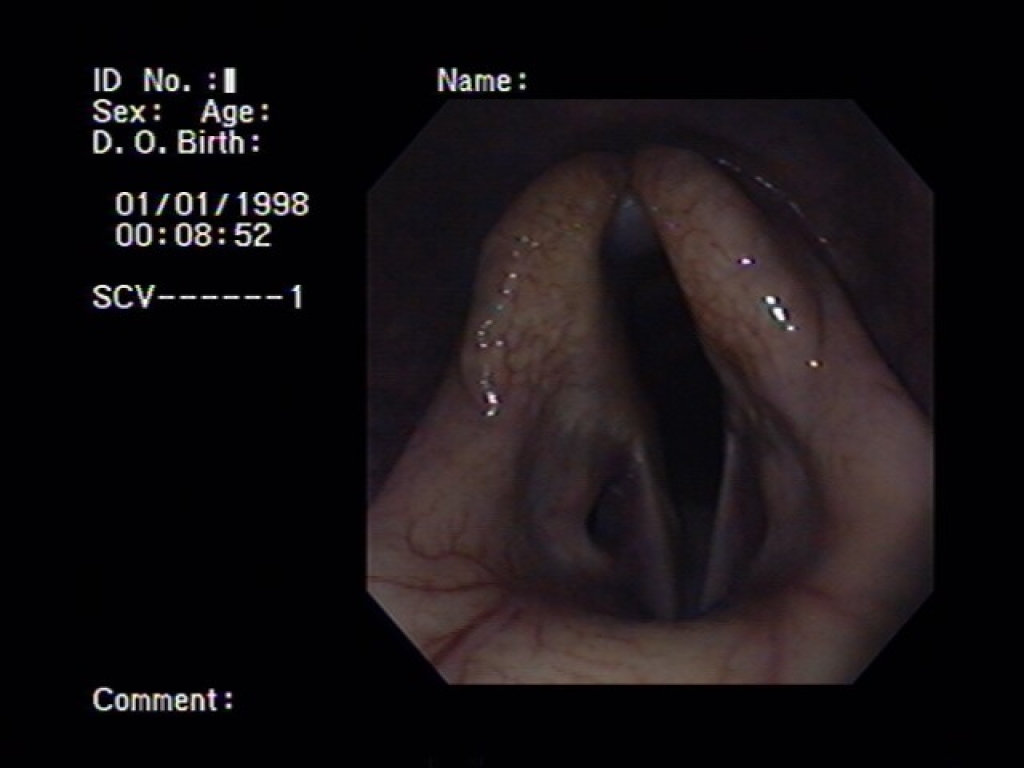

Linksbovenin is de keelholte in beeld gebracht. Rechtsboven is het strotteklepje met de stembanden daarachter van dichtbij in beeld gebracht. Het linker plaatje is van de luchtpijp.